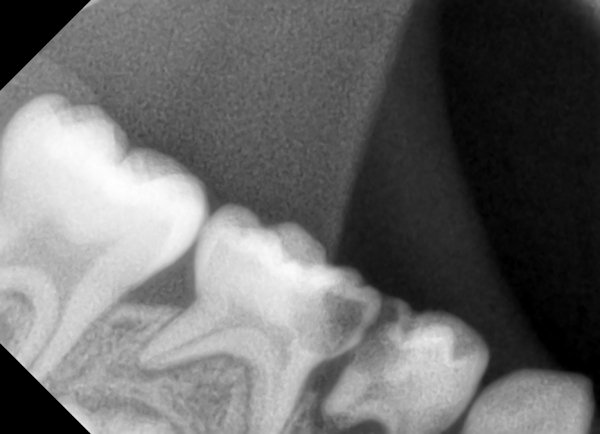

Доброе утро! Мне делали снимок в 14 лет, сказали у меня молочные зубы еще 2. Сказали сами выпадут. Сейчас мне уже почти 19. Один только шатается, болит жуть как. И над ним шишечка на десне, белая немного. Мне его нужно выдирать или сам выпадет? И еще я проживаю м.Петровско-Разумовская, Дмитровское шоссе 43-1. Мне если что в вашу поликлинику идти? Просто с детской, я так ни разу и не ходила к стоматологу.

Шишечка - это воспаление, зуб необходимо удалить.